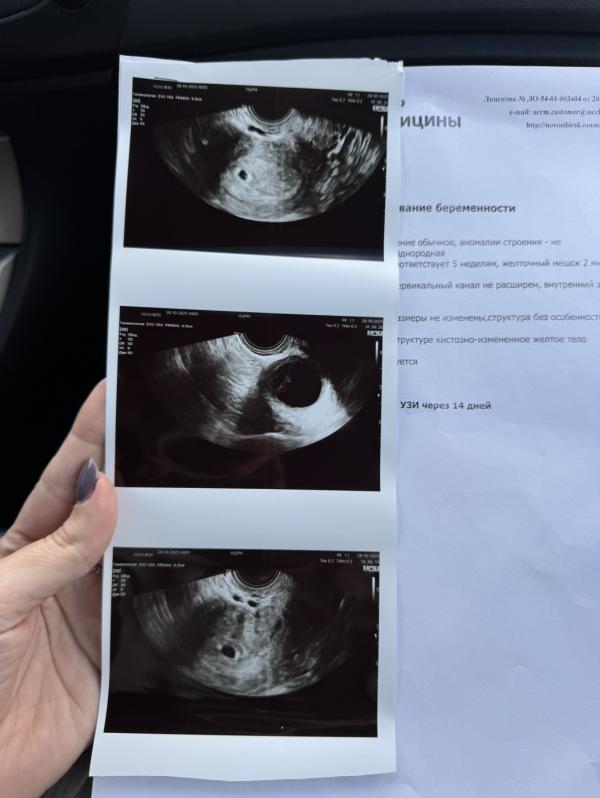

Первая встреча с малышом 🥲 такой мааааленький 🥹

Многие мои знакомые советовали клинику «Мать и дитя», съездили на первое узи- подтвердилась беременность. 5 нед. Но сердечко пока не слышали. Врач наша очень приятная и компетентная женщина- Чурина А.О. Скорее всего беременность тоже буду вести у них- тем более сейчас акция -20% на ведение в филиале на Кирова. А про роды не знаю, кто рожал там, стоит ли брать? Знакомая недавно родила в Академе по платной опции, довольна как слон. вообщем напишите как у вас с родами платными. ЖК и гос больницы прям очень не люблю, были неприятная история с аппендицитом, и это породило определенные страхи.